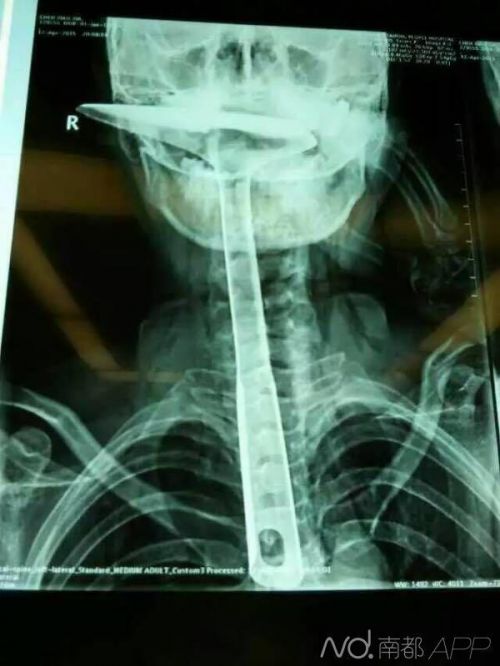

陳女士被緊急送到東莞第五人民醫院,醫生拍片顯示,整個鐵鍋鏟把手已經在胸里了,病情嚴重。當晚,陳女士就被轉到了康華醫院。“患者來院時,嘴巴里只剩一個鍋鏟鏟勺露在外面,整個鍋鏟手柄已經被插入到食道里了。”康華醫院胸外科接診醫生陳羽彪說,檢查發現,鍋鏟總長大概30公分長,手柄直徑約2.5公分,整個已經插入食道,食道表皮粘膜損傷嚴重,且被捅破了一個洞,“而且,手柄已嚴重擠壓到了肺部,導致右肺部已無法正常擴張。”

“這樣的病例,不說100年難遇,也是50年難遇了。”康華醫院胸外科主任肖樸說,患者情況嚴重,醫院立即組織專家會診。“胸腔全是大血管,一旦拔出就有可能大出血,危及性命。”當天晚上11點,醫生決定為患者進行一期手術即食道擴置手術,“我們先將鍋鏟從食道里面拔出來,由于胸位食道受損嚴重,只能切除了。”

醫生介紹,食道總長約25公分,患者切除了20公分,切除部分主要集中在胸位段,食道只保留到了頸部,只能露出來進行醫學處理,吞咽口水、積液進行人工及時清理更換。”